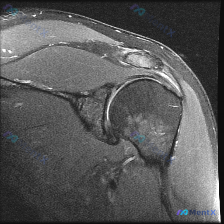

最近看到一个肩关节病例,资料里主要有一张肩关节冠状位T2加权MRI。患者可能有肩部症状,假设是盂唇病变,但影像上的表现有点矛盾。先放影像分析的核心点: 1. 盂唇结构:关节盂上、下边缘的盂唇信号正常,边缘锐利,未见高信号裂隙或旁囊肿,没看到典型的盂唇撕裂征象。 2. 肩袖肌腱:冈上肌肌腱附着于肱骨大...

整理了一个肩关节MRI病例,临床问题是评估盂唇病变,但影像分析有几个点值得讨论: 1. 冈上肌腱在肱骨大结节附着处信号增高,结构连续性似乎中断 2. 肩峰下-三角肌下滑囊有明显积液 3. 肱骨大结节区域有骨髓水肿 4. 报告提到“冠状位无法全面评估盂唇” 大家第一眼会更倾向于哪个诊断?